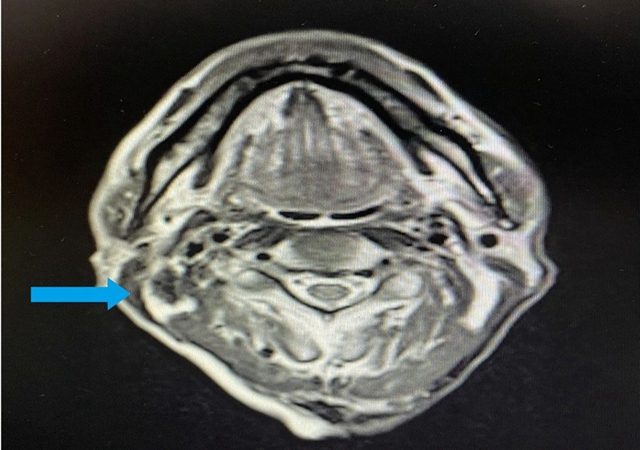

鼻咽部核磁共振:鼻咽部粘膜明显增厚(右侧为甚),鼻咽腔变窄,符合鼻咽癌变表现,双侧颈部多发淋巴结增大转移,右侧为多;

综合检查结果,西医诊断为:鼻咽部恶性肿瘤(分化型非角化性癌)侵及口咽、咽旁间隙伴咽后、颈部转移淋巴结;肺继发恶性肿瘤;中医诊断为鼻咽癌(痰瘀互结)。

治疗3月后,李大叔复查胸部CT与上次比较,肺部结节缩小,大小约1.6×1.3cm²;复查鼻咽部MRI提示:鼻咽部病灶明显缩小,右侧咽旁间隙肿大淋巴结未见显示,颈部双侧淋巴结数量减少、体积缩小。